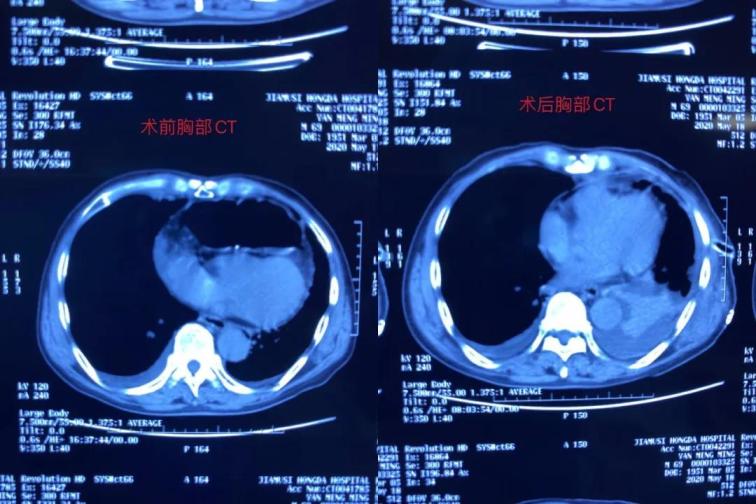

雖然患者表現(xiàn)為腸梗阻癥狀,但是從事普外多年、細(xì)心的張醫(yī)生對(duì)患者的胸部CT心前區(qū)顯示低密度影像產(chǎn)生疑問(wèn),懷疑膈疝可能,并于5月12日晨找胸外科周鋼主任會(huì)診。 周鋼主任結(jié)合病史、癥狀、查體、輔助檢查,高度懷疑膈疝中的心膈角疝,疝內(nèi)容物考慮結(jié)腸可能,因患者目前表現(xiàn)為腸梗阻,腸管卡壓時(shí)間長(zhǎng)易導(dǎo)致壞死,且胸部CT表現(xiàn)心包填塞,此時(shí)動(dòng)脈血壓已經(jīng)下降,靜脈血壓升高,脈壓差縮小,已經(jīng)出現(xiàn)休克。

術(shù)中發(fā)現(xiàn)橫結(jié)腸疝入心包并嵌頓,腸管高度擴(kuò)張,已經(jīng)顏色較暗,同時(shí)疝入心包腔內(nèi)還有大網(wǎng)膜,已表現(xiàn)血運(yùn)障礙。心臟嚴(yán)重受壓,近乎停止跳動(dòng)。緊急切開(kāi)擴(kuò)大疝環(huán),觀察疝入的腸管和大網(wǎng)膜血運(yùn)情況,約觀察30分鐘血運(yùn)障礙恢復(fù)后,小心將疝入的腸管和大網(wǎng)膜還納入腹腔。心包腔恢復(fù)原有空間,心臟開(kāi)始恢復(fù)節(jié)律性跳動(dòng)。術(shù)后病人轉(zhuǎn)入胸外科病房,監(jiān)護(hù)綜合治療護(hù)理,目前患者恢復(fù)良好。

胸腹腔疝多為膈疝,疝入部位為胸腔,未見(jiàn)有疝入心包內(nèi)、壓迫心臟的病歷。正常心包腔內(nèi)除心臟外無(wú)容納空間,罕見(jiàn)腹腔臟器疝入。此患者屬罕見(jiàn)病例,搶救成功的關(guān)鍵在于多學(xué)科的合作、手術(shù)的及時(shí),否則心包填塞可隨時(shí)導(dǎo)致心臟驟停甚至死亡。